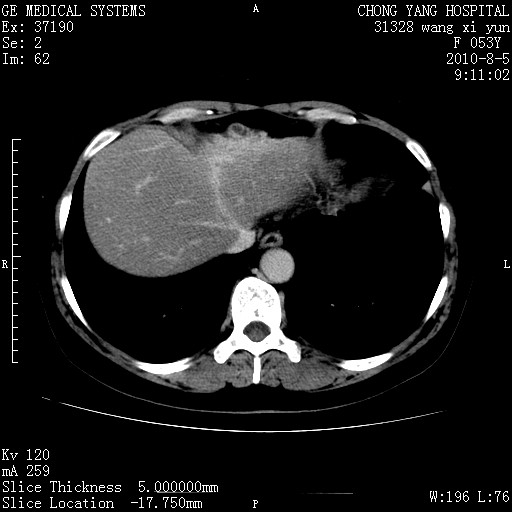

标题: CT28214:F41Y 血尿二十天,建议盆腔平扫加增强。

胆管细胞ca?

1)考虑肝左叶胆管细胞癌。2)脂肪肝。

支持胆管细胞ca。